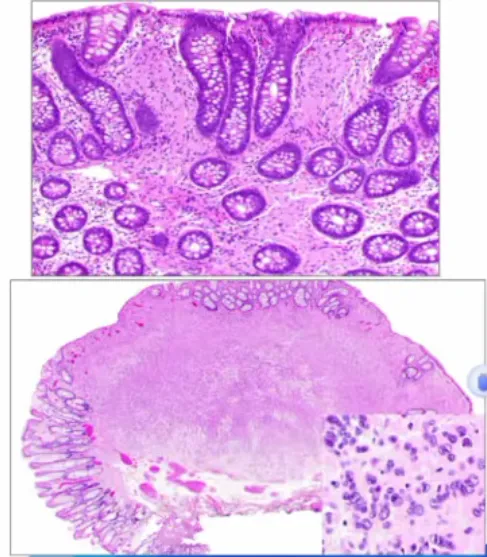

单纯黏液性囊肿 新增

• 定义:大于10mm的腔状病变,由胃型上皮组成无乳头状结构和卵巢型间质

• 镜下:

1.内衬单层立方到柱状上皮,至少局灶性为黏液性,含胃型黏液;

2.扁平状排列,很少乳头状;

3.缺乏卵巢样间质及淋巴细胞带;

4.可存在退行性改变;

5.背景中常见PanlN(<5mm)。